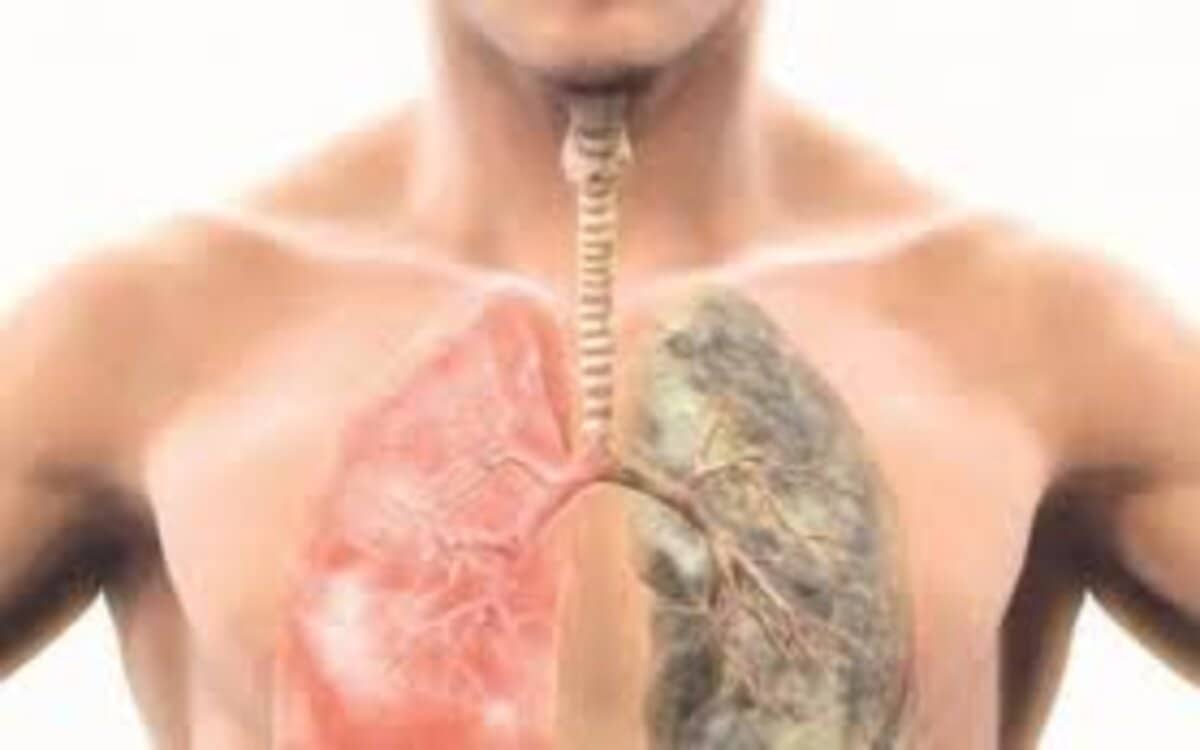

يعد مرض تليف الرئة من أكثر الحالات غير معروفة سبب الإصابة بها، لذلك يطلق عليه الأطباء “مرض التليف الرئوي المجهول”، ولكنه مرض مزمن يصيب الرئتين، ويحدث نتيجة تلف أنسجة الرئة وضمورها، ويفقد الرئة وظيفتها الأساسية وهي تحميل الدم بالأكسجين وتخليصه من ثاني أكسيد الكربون.

ليس هناك سبب واضح ومحدد للإصابة بتليف الرئة، ولكن هناك العديد من العوامل المختلفة التي تؤدي إلى تلف الأنسجة المحيطة بالحويصلات الهوائية والتي تفصل بين الرئتين، وتسبب صعوبة انتقال الأكسجين إلى الدم، ومن أبرز الأسباب التي تؤدي إلى تليف الرئة ما يلي :